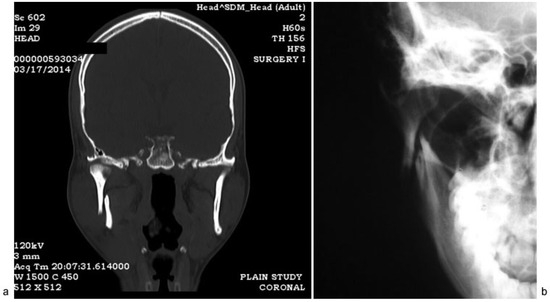

Figure 1.

(a) Coronal section through temporomandibular joint, (b) PA mandible shows laterally displaced condyle.